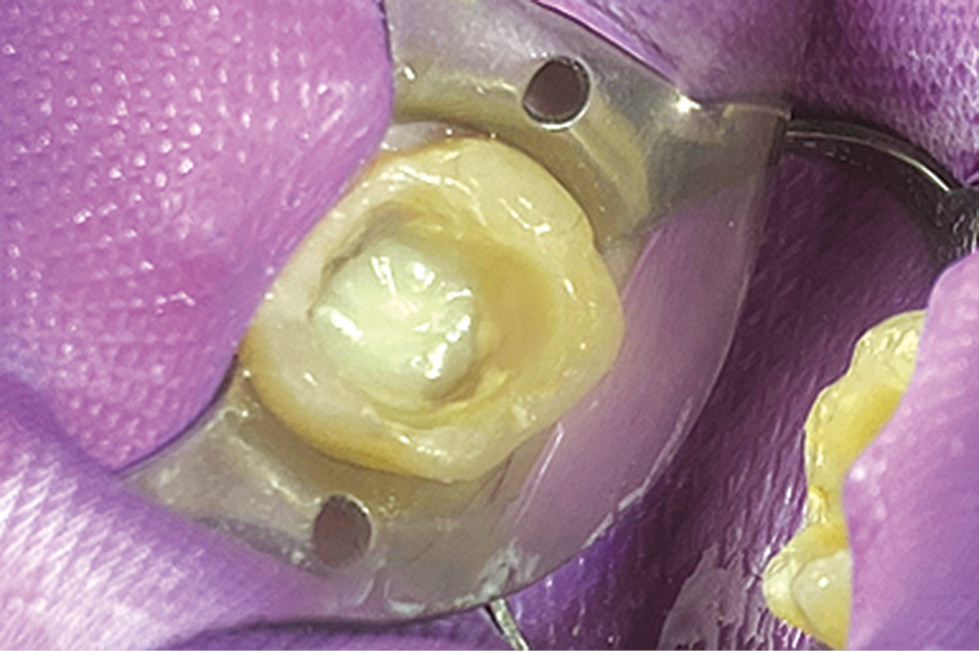

План лечения: удаление несостоятельной реставрации 4.6, проведение прямой композитной реставрации зуба 4.6 с использованием «Гусеницы». Учитывая значительные дефекты твёрдых тканей на контактной и жевательной поверхности зуба 4.6 и бруксизм, представляется важным армирование стенок зуба и восстановление с помощью нити с композитом.

Проведено лечение: наложение изоляционной системы, под мандибулярной анестезией раствором артикаина 1 мл и водо-воздушным охлаждением удалена временная реставрация зуба 2.7, поверхность препарирована для изготовления прямой композитной реставрации. Проведено селективное протравливание эмали и нанесение адгезивной системы 7-го поколения Uni Bond Universal (IDS)1 (рис. 12), далее проведено армирование стенок зуба «Гусеницей» методом циркулярной конденсации нити по всему периметру полости (рис. 13). Дальнейшая прямая реставрация проведена наногибридным универсальным композитом Boston, который входит в состав «Гусеницы». Материал имеет повышенную механическую прочность для пломбирования жевательной группы зубов (рис. 14).

Рис. 12. Обработка полости зуба самопротравливающей адгезивной системой 7-го поколения Uni Bond (IDS).

Fig. 12. Treatment of the tooth cavity with a 7th generation selfetching adhesive system Uni Bond (IDS).

Рис. 13. Конденсация «Гусеницы», армирование стенок зуба 2.7.

Fig. 13. Caterpillar condensation, reinforcement of the walls of tooth 2.7.

Рис. 14. Итоговая реставрация зуба 2.7.

Fig. 14. Final restoration of tooth 2.7.